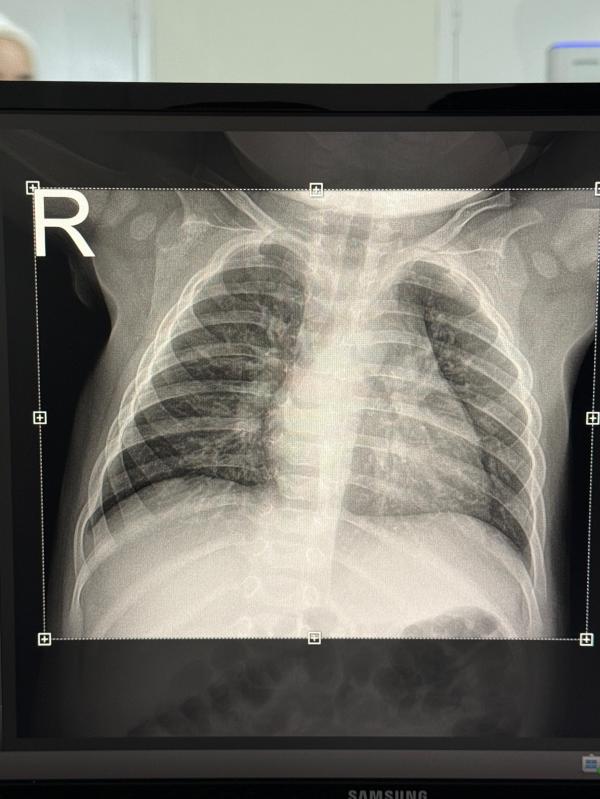

Девочки сказали что нет пневмонии,но есть обструкция,это что?

Обструкция лёгких — это сужение или блокировка дыхательных путей, что затрудняет прохождение воздуха в лёгкие и из них. Из-за этого возникают затруднённое дыхание, одышка, кашель и свистящие хрипы. Часто наблюдается при астме, хроническом бронхите и других заболеваниях дыхательной системы. Можно сказать, что это "пробка" или "сужение" в дыхательных путях. Если хочешь, могу найти точное определение с медицинских ресурсов. Хотел бы?

Просвет йол меттиг юй и юкх очаг воспаление